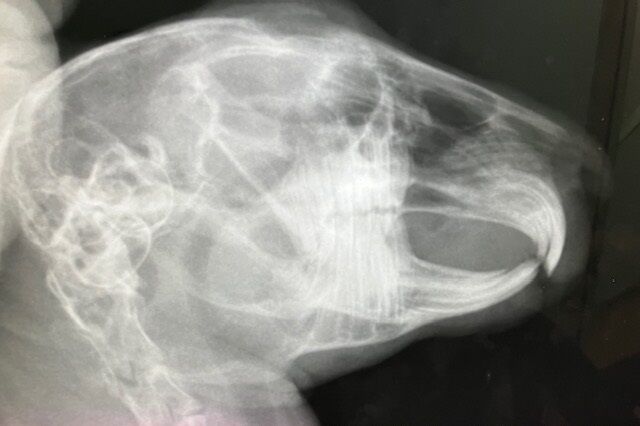

術前検査のレントゲン

特に問題ありません。

※クリックで拡大見れます。

切歯もキレイ